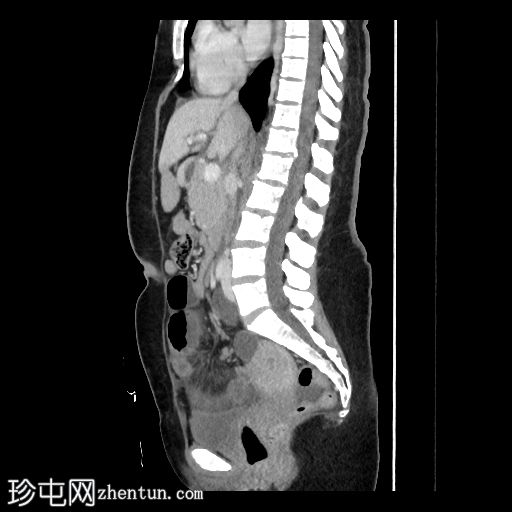

CT扫描

2.jpg

轴位增强扫描(门静脉期)

多处回肠袢扩张,最大直径约3.3厘米,累及约46厘米肠段

可见两个移行区,一个位于近端,一个位于远端,扩张肠段位于两者之间

部分扩张肠袢肠壁强化减弱,提示肠缺血

远端移行区附近可见肠系膜血管呈旋涡状,即“漩涡征”

道格拉斯窝和子宫膀胱窝内可见少量盆腔游离液体

一位既往健康​​的40岁女性因进行性腹痛、腹胀和便秘3天就诊于急诊科。她自述既往有胆囊切除术和剖宫产史。行立位腹部X线片检查,显示多处小肠袢扩张并伴有气液平面。紧急行腹盆部增强CT检查,结果显示闭袢性小肠梗阻伴早期缺血征象。随后行紧急腹腔镜检查,发现粘连带造成梗阻,并证实CT所见的肠缺血,遂行肠段切除吻合术。

CT典型表现包括扩张的充满液体的肠袢、肠系膜血管扭曲形成的“漩涡征”,以及肠壁增厚、肠系膜水肿或腹水等。这种肠袢形态具有较高的缺血和绞窄风险,如不及时治疗,可能导致肠坏死。